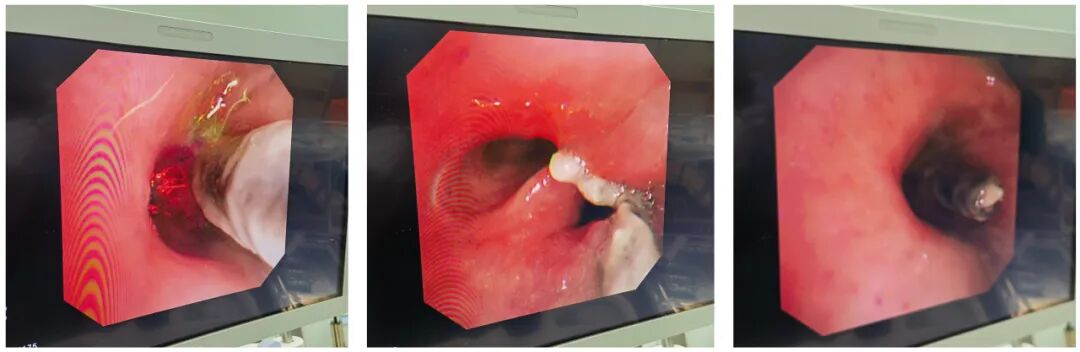

准备妥当后,呼吸内科张雷副主任医师为徐女士进行了支气管镜检查,结果发现患者的右侧支气管内果然有异物存在,且异物下端已经插入支气管壁,而周围有明显的充血水肿,并伴有肉芽生成。

张雷医师尝试钳除,但异物下端固定得很深,稍有触碰就出血明显。考虑到盲目拔除容易引起大出血危及生命,呼吸介入团队随即进行了讨论,后决定,改为全麻下在手术室进行异物取出。

完善一系列准备措施后,呼吸内科主任助理王嫔副主任医师、张雷副主任医师,与麻醉科主任杨天革、内镜中心护士长陈玲君通力合作,为徐女士实施了手术,通过剥离部分包绕异物的肉芽后成功取出了异物。

此异物长达2CM左右,呈黑褐色,疑似鸭骨。